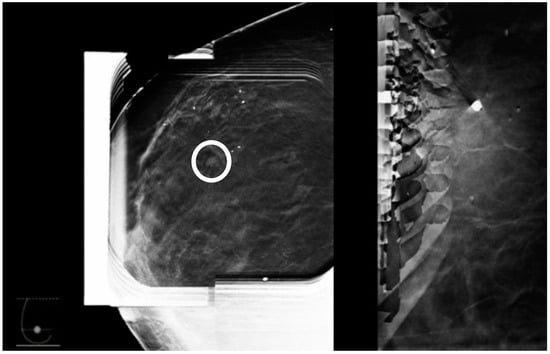

The site of entry in this approach should be determined based on the location of the lesion dictating the shortest skin-to-lesion route. For example, when the lesion is closest to the superior aspect of the breast, a cranio-caudal (CC) approach is favored (Figure 1).

Figure 1. (AD) represent four possible approaches for biopsy of a lesion located in the upper inner aspect of the breast. (C) is the shortest skin-to-lesion route, so a craniocaudal approach should be used.